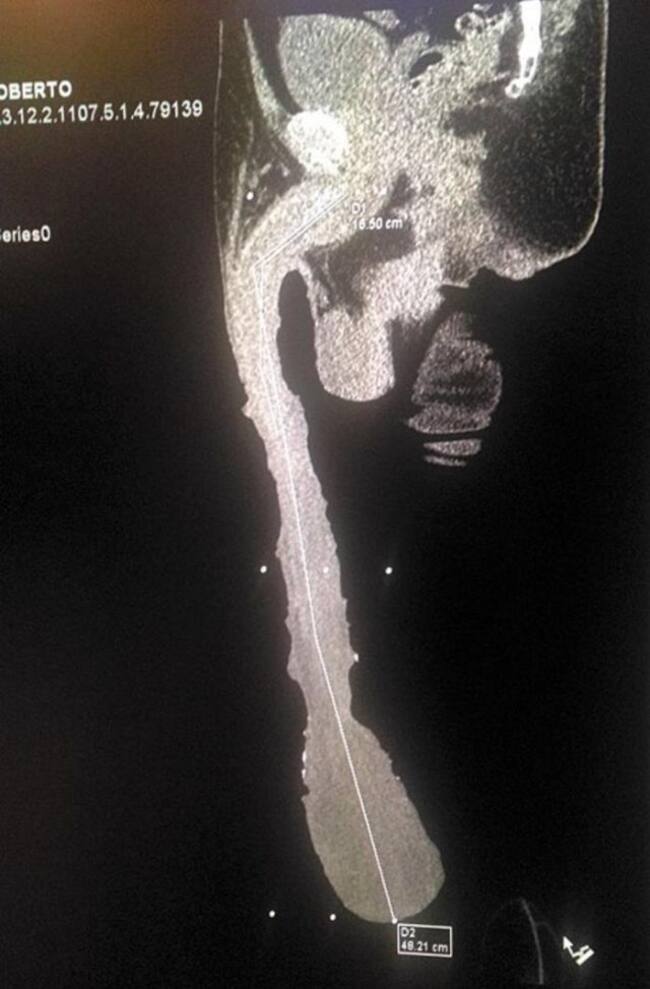

El hombre con el aparato reproductor más grande con un tamaño de 48.2 cm

Los médicos determinaron que 32 centímetros son de piel que creció de manera extraordinaria; falta determinar si este crecimiento es por causas artificiales y los riesgos que implica.